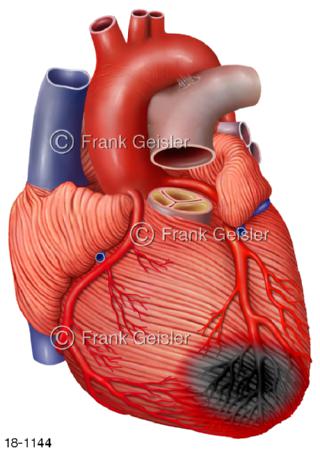

18-1144 Herzerkrankung Herzinfarkt Herzmuskelinfarkt